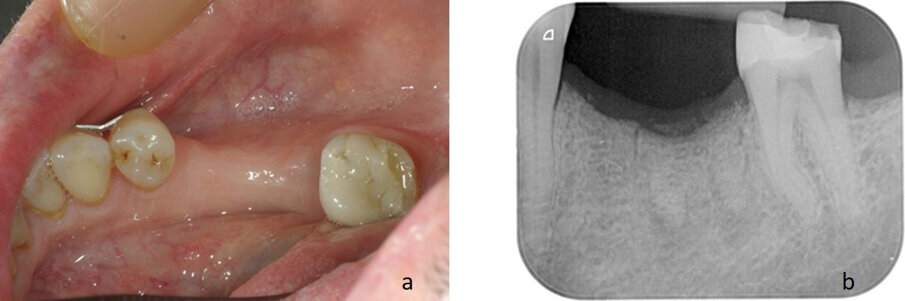

Il paziente è un uomo di 53 anni, non fumatore, che si è presentato all’osservazione del chirurgo con un molare (3.6) compromesso a causa di una frattura verticale, lamentando dolore alla masticazione. Al paziente era stato proposto inizialmente di eseguire una riabilitazione attraverso una corona posizionata su di un impianto post-estrattivo immediato. Il paziente tuttavia aveva rifiutato l’intervento proposto a causa di preoccupazioni economiche, preferendo rimandare in futuro l’inserimento implantare. Si è quindi optato per l’estrazione dell’elemento compromesso e per la conservazione, per quanto possibile, dei volumi ossei attraverso l’utilizzo di un innesto osseo e mediante il posizionamento di una membrana, secondo i principi della ridge preservation. Il paziente ha acconsentito al trattamento e ha fornito il proprio consenso informato (Figg. 1, 2).

Fig. 1 - Radiografia endorale. L’elemento 3.6 è compromesso a causa di una frattura e deve essere estratto.

Fig. 2 - Aspetto clinico dell’elemento prima dell’estrazione, vista linguale.